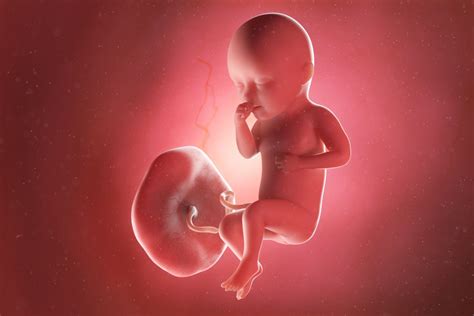

Începând cu săptămâna 8 de sarcină, viitorul bebeluș este denumit fetus. Picioarele i se lungesc, chiar dacă diferitele segmente ale membrelor nu sunt, încă, distincte. Placenta continuă să se formeze, pregătindu-se să se atașeze de peretele uterin.

Dezvoltarea fătului de la săptămâna 10 la săptămâna 15

Pe măsură ce sarcina avansează, embrionul devine fetus și începe să capete trăsături din ce în ce mai umane, iar corpul mamei continuă să se adapteze.

Fătul are acum 9-10 cm și 45-100 grame; el este, mai mult sau mai puțin, format complet și tot ce mai are de făcut este să crească și să se matureze.

Placenta începe să preia producția de hormoni; devine ușor de aflat dacă fătul nostru este băiat sau fată. Corpul este acoperit cu firicele fine de păr, numit lanugo, care protejează pielea foarte sensibilă și dispare târziu, spre sfârșitul sarcinii. Pielea este protejată și de un strat de grăsime, cu rol în termoreglare numită vernix caseosa.

Fătul își poate suge degetul acum, iar tu începi să capeți alura de femeie însărcinată. E timpul să-ți cumperi alte haine.